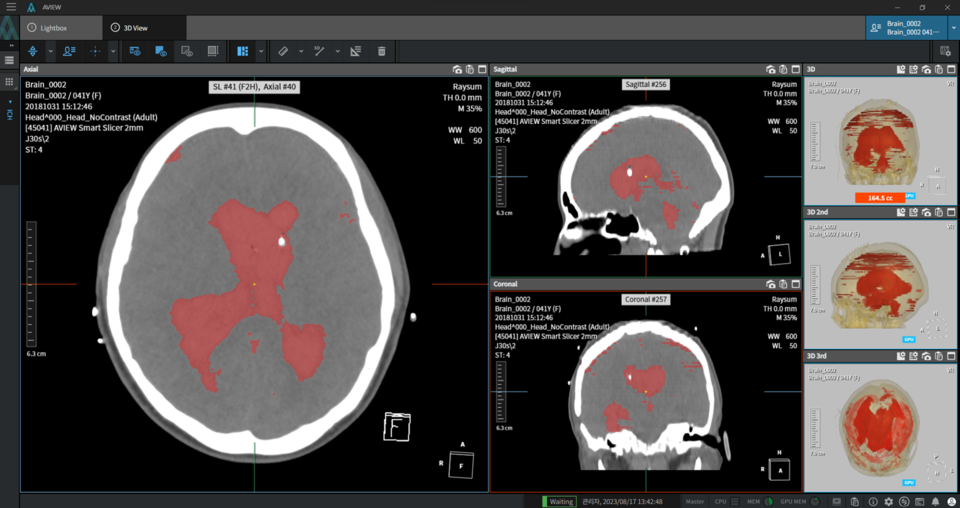

코어라인소프트에 따르면, 에이뷰 뉴로캐드는 환자 CT이미지를 기반으로 제한된 시간 내 영상을 판독하고 진단·치료 결정까지 할 수 있도록 지원하는 솔루션이다. ▲출혈이 많은 영상부터 환자군 정렬 ▲출혈량에 따른 우선 병변부 정보 제공 ▲뇌출혈 의심 부위 미리보기 기능을 통해 응급환자에 대한 판독 우선순위도 제시할 수 있다.

2D와 3D영상을 비교할 수 있고 의료기관의 판독시스템(PACS)과도 연동되는 것도 특징이다.